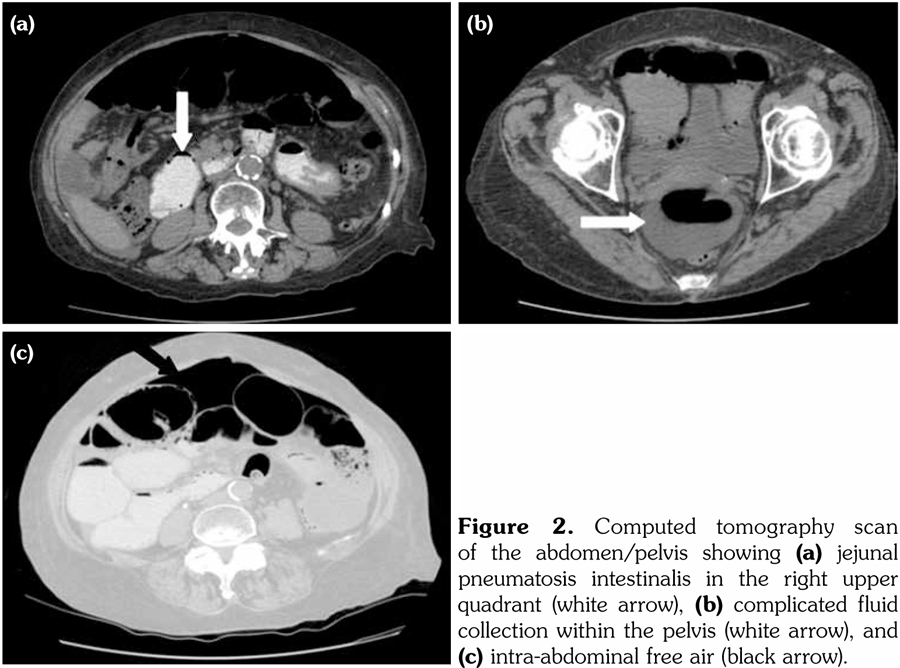

An abdominal computed tomography (CT) scan revealed large volume intra-abdominal free air, moderate intra-abdominal free fluid with no extravasated contrast, pneumatosis of the proximal jejunum with dilatation up to 5.8 cm, and a transition point (Figure 2). These findings raised concern for acute bowel ischemia, volvulus, and possible perforation.

However, given the patient’s comorbidities, stable condition and lack of peritonitis, the general surgeon recommended conservative management with intravenous fluids and bowel rest. A repeat CT scan on post-admission day two revealed resolution of the pneumatosis and focal volvulus, but persistent intra-abdominal free air and free fluid. She was started on oral amoxicillin and metronidazole for possible SIBO and discharged on post-admission day three. She was reviewed in clinic shortly thereafter, at which point her clinical condition remained stable.